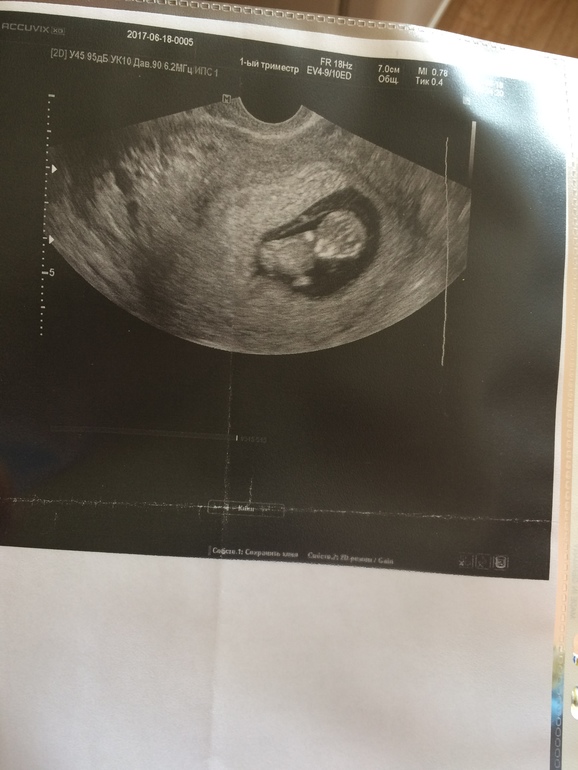

По УЗИ срок 10 недель

А какой у вас ктр?

14.09.2017

Был 54